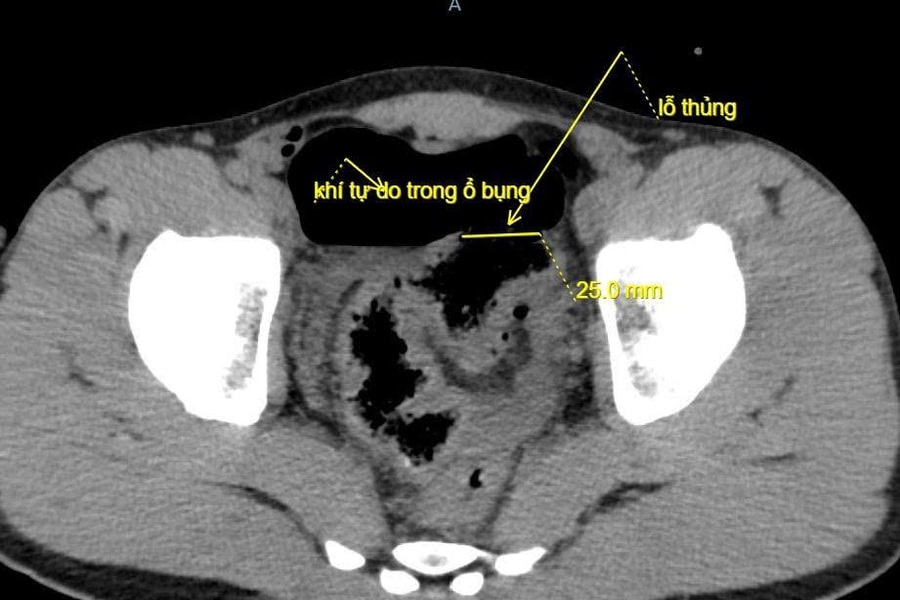

Hy hữu: Trêu đùa bằng vòi xịt rửa xe gây thủng đại tràng

Một trò đùa thiếu an toàn khiến nam thanh niên bị thủng đại tràng, phải phẫu thuật cấp cứu để giữ tính mạng.